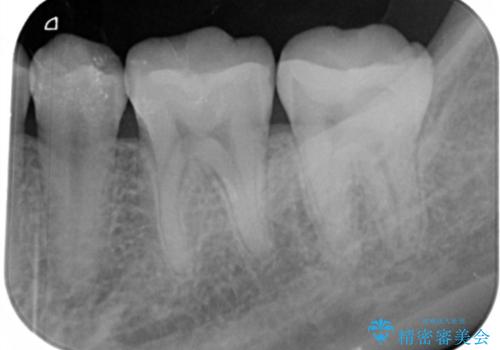

- 左下6、7番の虫歯をセラミックにて治療を希望された患者様です。

切削量を考慮してセラミックインレーを選択しました。

7番は虫歯が深かったのでCR裏層した上で形成、印象をしています。